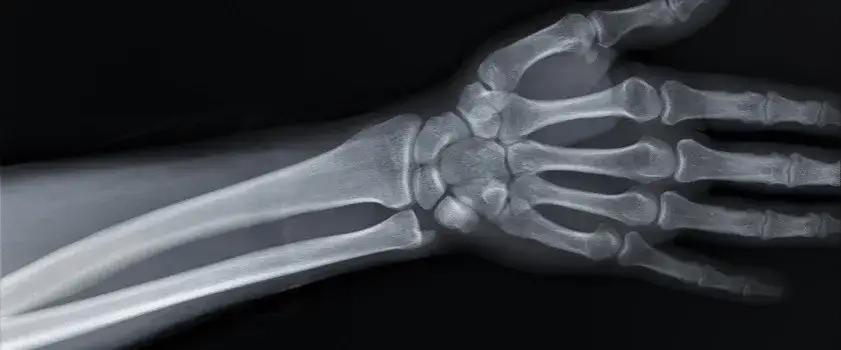

Czy złamana ręka puchnie? Objawy, leczenie i rehabilitacja

Dowiedz się, czy obrzęk po złamaniu ręki jest normalny. Poznaj przyczyny, objawy i skuteczne metody leczenia opuchlizny. Sprawdź, kiedy skonsultować się z lekarzem.